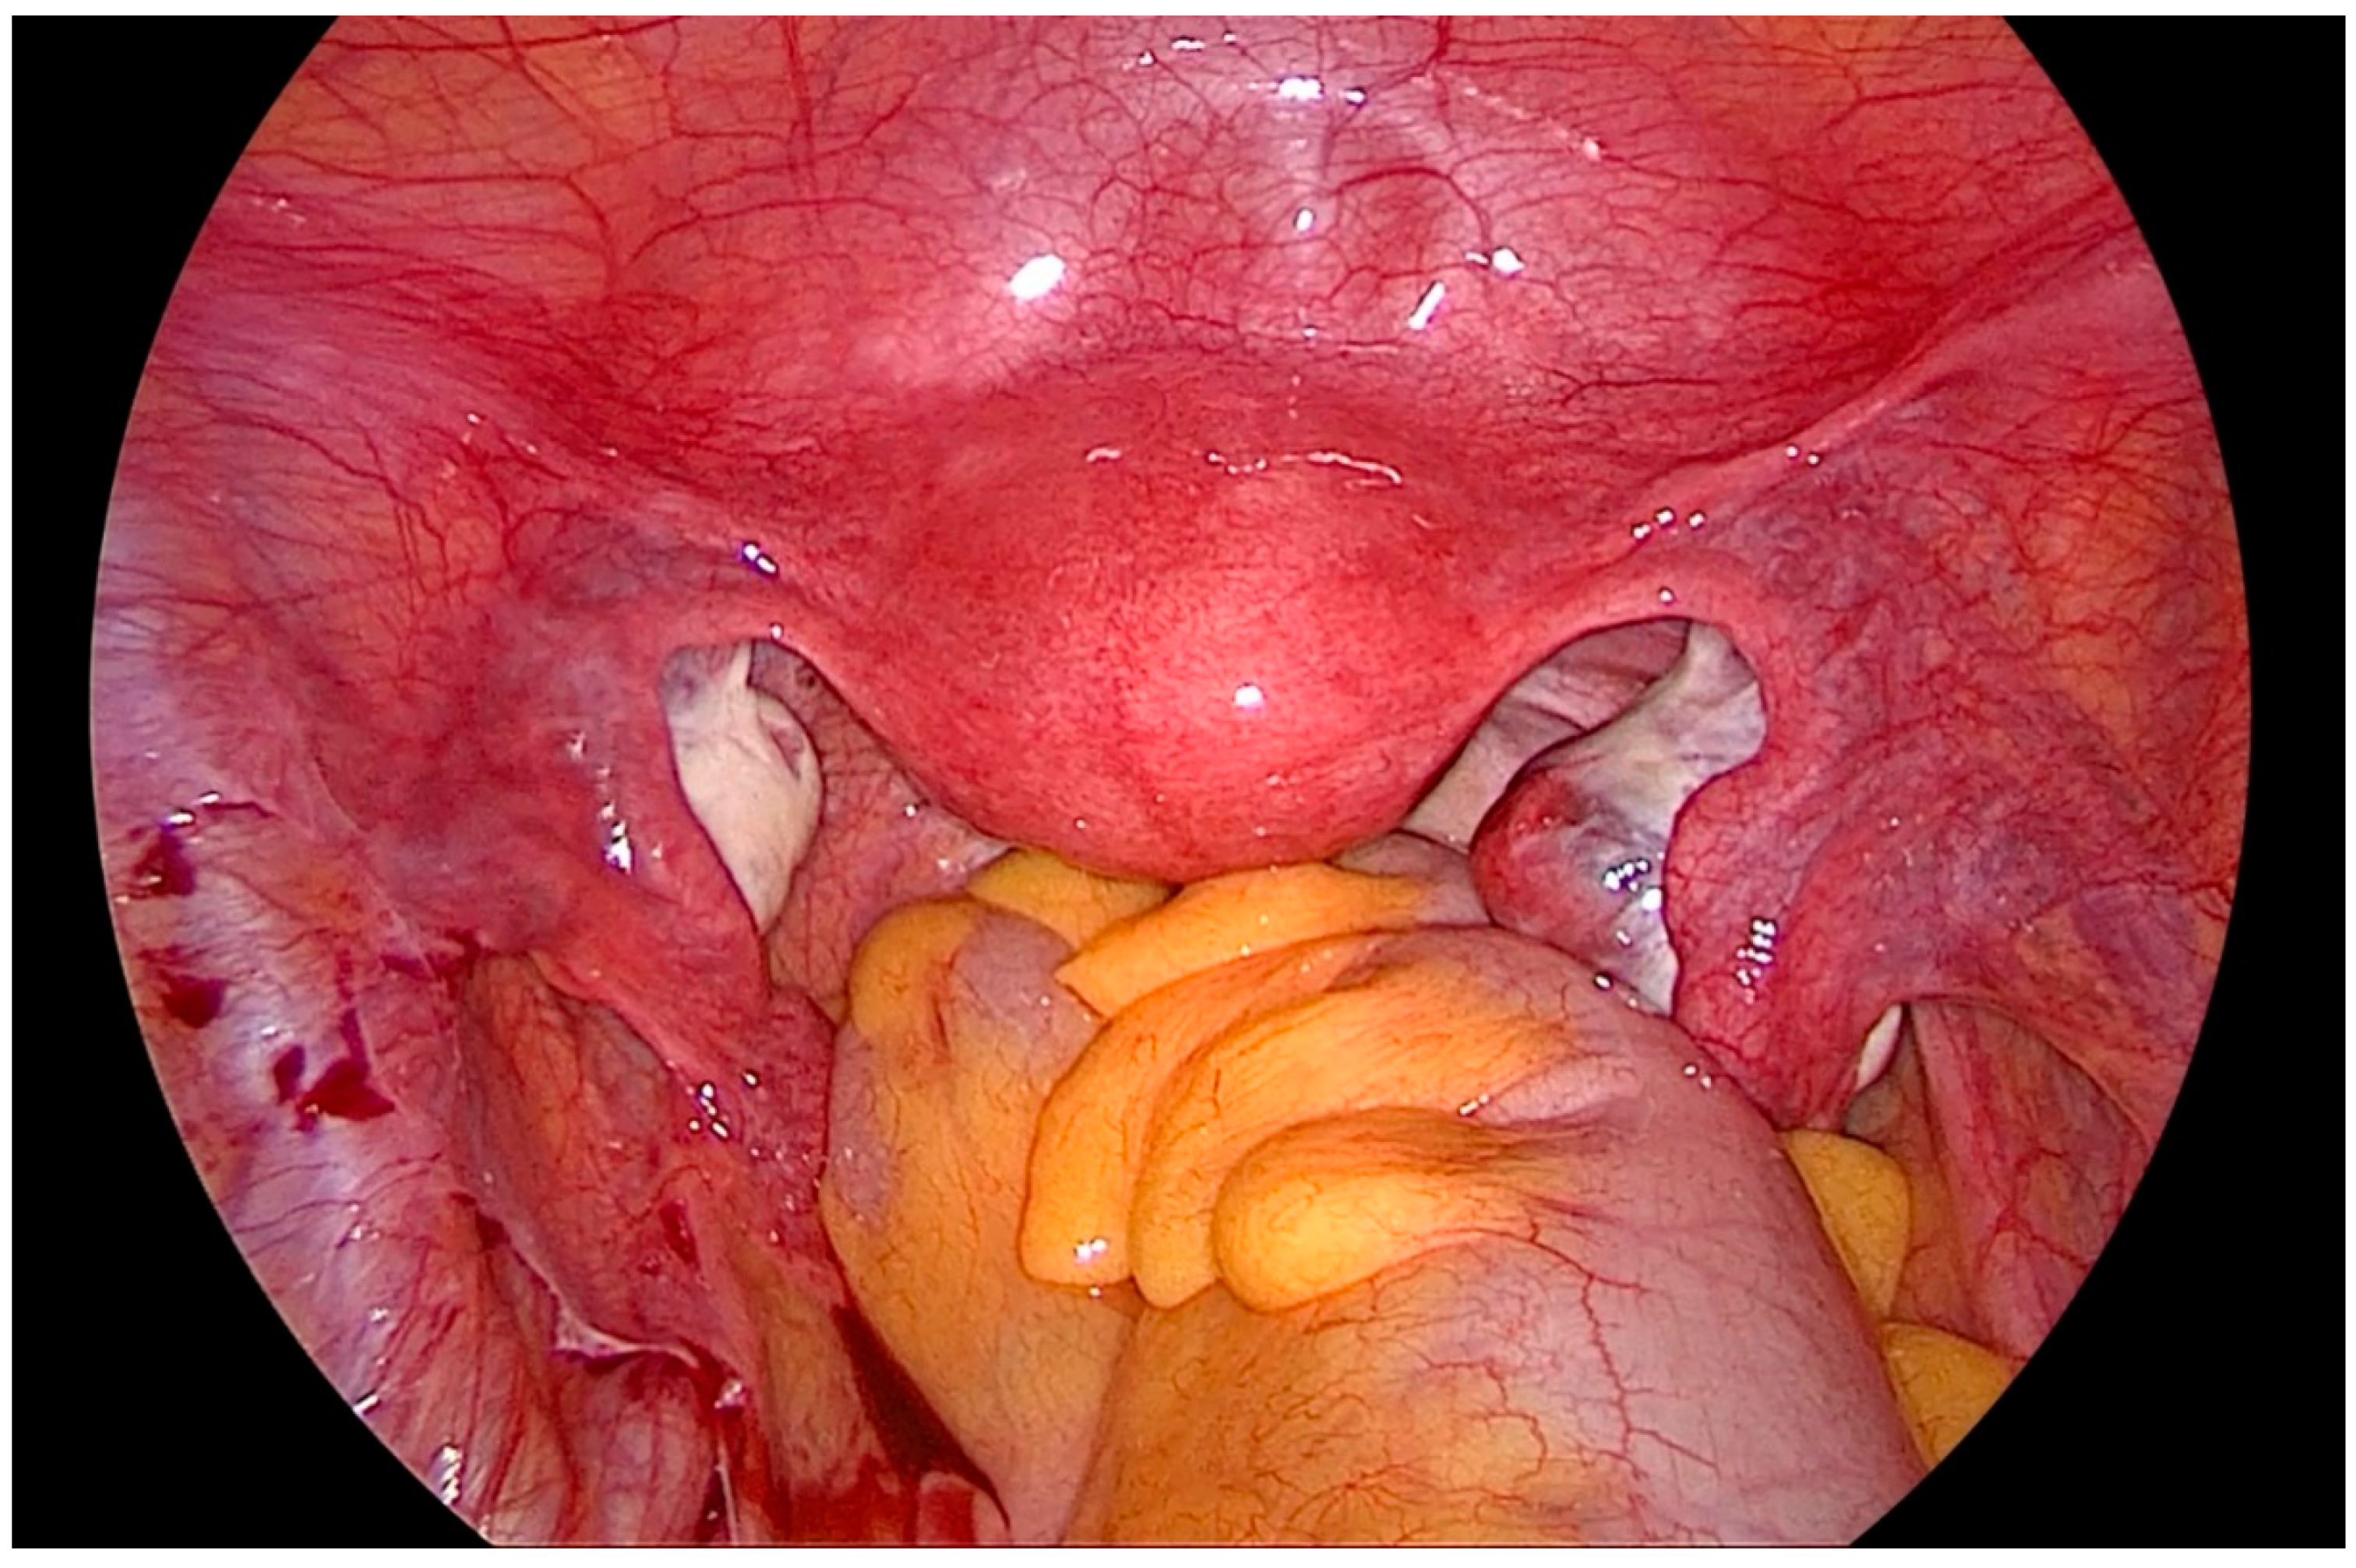

After gaining access to the peritoneal cavity laparoscopically (Figure 1), the cavity is thoroughly investigated for endometriotic cysts, spots, and adhesions. If an endometriotic ovarian cyst is found, it is excised. If endometriotic spots or nodules are found underneath the ovary on the ovarian fossa, or uterosacral ligaments, the ipsilateral ovary is suspended to the anterior abdominal wall (Figure 2). A straight needle with a single monofilament non-absorbable thread is passed through the lower anterior abdominal wall. Prior to insertion of the needle, the inferior epigastric vessels should be located to avoid injury and hematoma formation. The needle is retrieved intra-corporeally by grasping it using a laparoscopic needle holder. It is then passed from the medial side of the ovary through the ovary into the abdominal wall close to the point where it was introduced. At this step also, it is essential to pay attention to the inferior epigastric vessels once more. The needle is then pulled out from the abdominal wall using a hemostat forceps. The two ends of the thread are tied extra-corporeally over a compressor gauze on the abdominal wall, with some tension, thus suspending the ovary to the abdominal wall with the medial side of the ovary apposed to the peritoneum of the anterior abdominal wall (Video S1).

Figure 1. Laparoscopic view of the pelvis, depicting the ovaries hampering vision and access to the lateral pelvic wall.